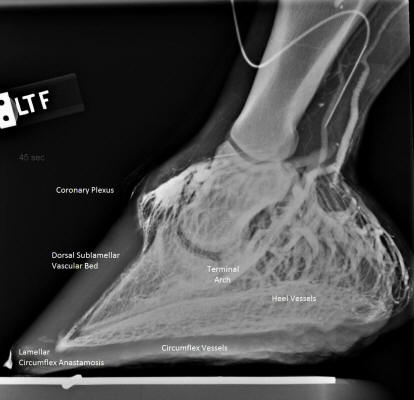

When Debra Taylor DVM, DACVIM (Auburn School of Veterinary

Medicine) and I first started working together we compared notes on this type of

case. Using venograms (see Figure 5), she had been noting a dramatic decrease in

circulation into the hoof capsule in cases that had more than ¾-inch CE, and

normal circulation in most horses with CEs less than ¾-inch. The two stories fit

together well—what I had seen in the field made sense.